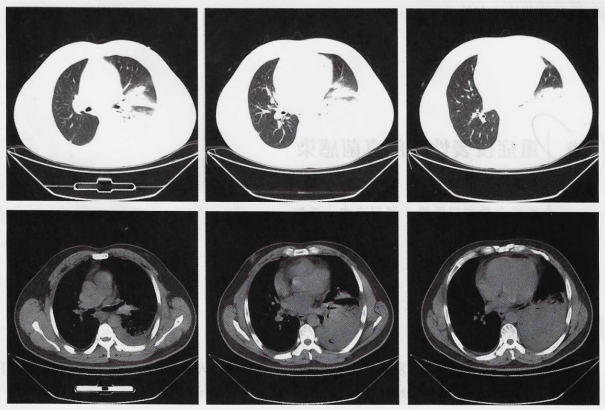

胸部CTPA1:左上肺后段及左下肺炎症伴左侧少量胸腔积液,建议复查;肺动脉CTA未见明显异常;附见肝内低密度影,囊肿?请结合其他检查。

图1  患者入院后胸部CT